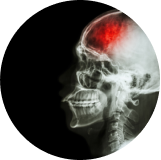

Estos signos y síntomas de la hipertensión arterial son variables, no necesariamente ocurren y pueden aparecer cuando la alta de la presión arterial pone en riesgo la vida. Los riesgos de estos niveles de presión arterial son:(2)

• Ataque cardíaco

Ataque cardíaco

• Accidente cerebrovascular (ACV)

Accidente cerebrovascular (ACV)